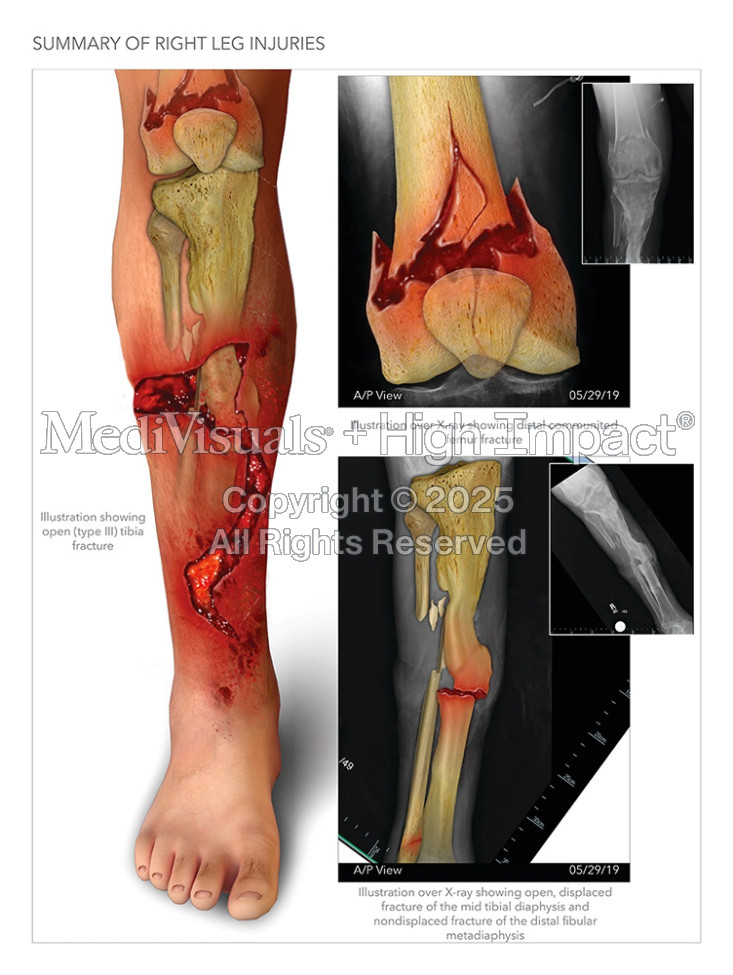

$1.15M Settlement: Illustrating Leg Fractures After Car Hits Man on Scooter

A man was driving a scooter when another vehicle drove onto the curve, ran him over, and catastrophically injured his right leg.